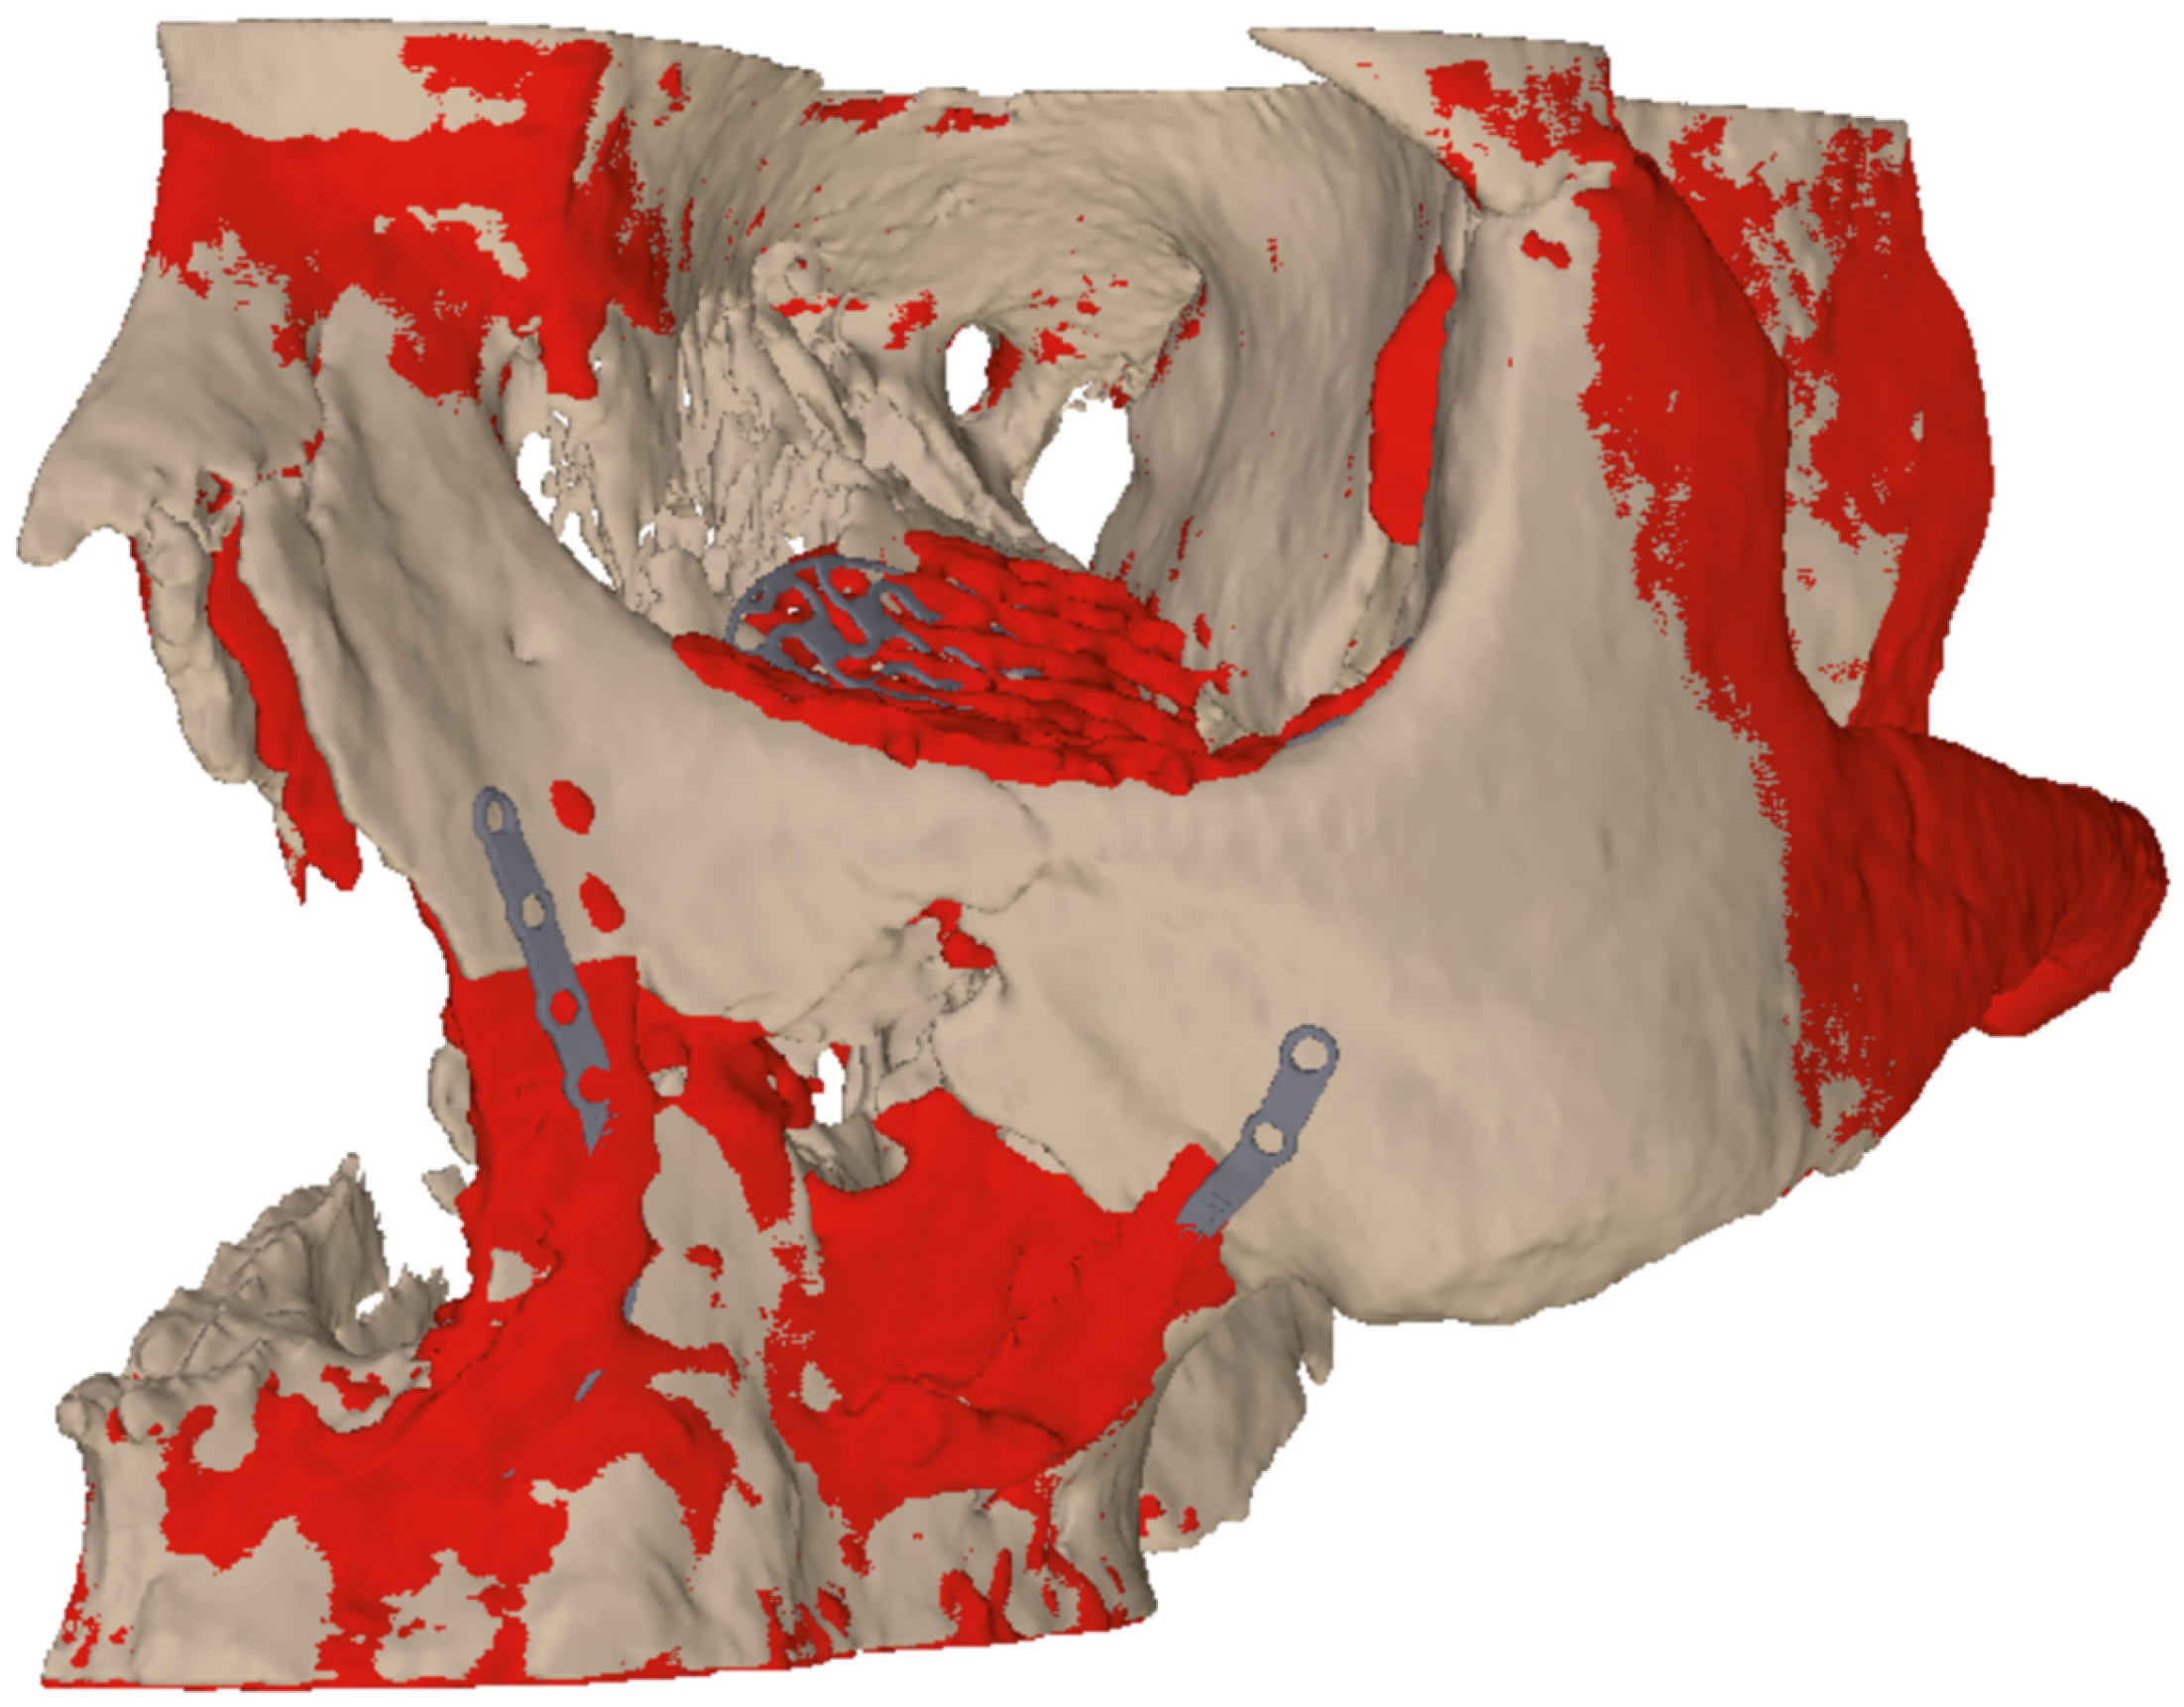

Figure 10a,b are showing the images of the intraoperative 3D C-arm scan and Figure 11 shows the image fusion between plan and achieved result.

Figure 11. Image fusion of 3D planning (beige) and post-operative situation (red) to illustrate the difference between virtual planning and achieved result.